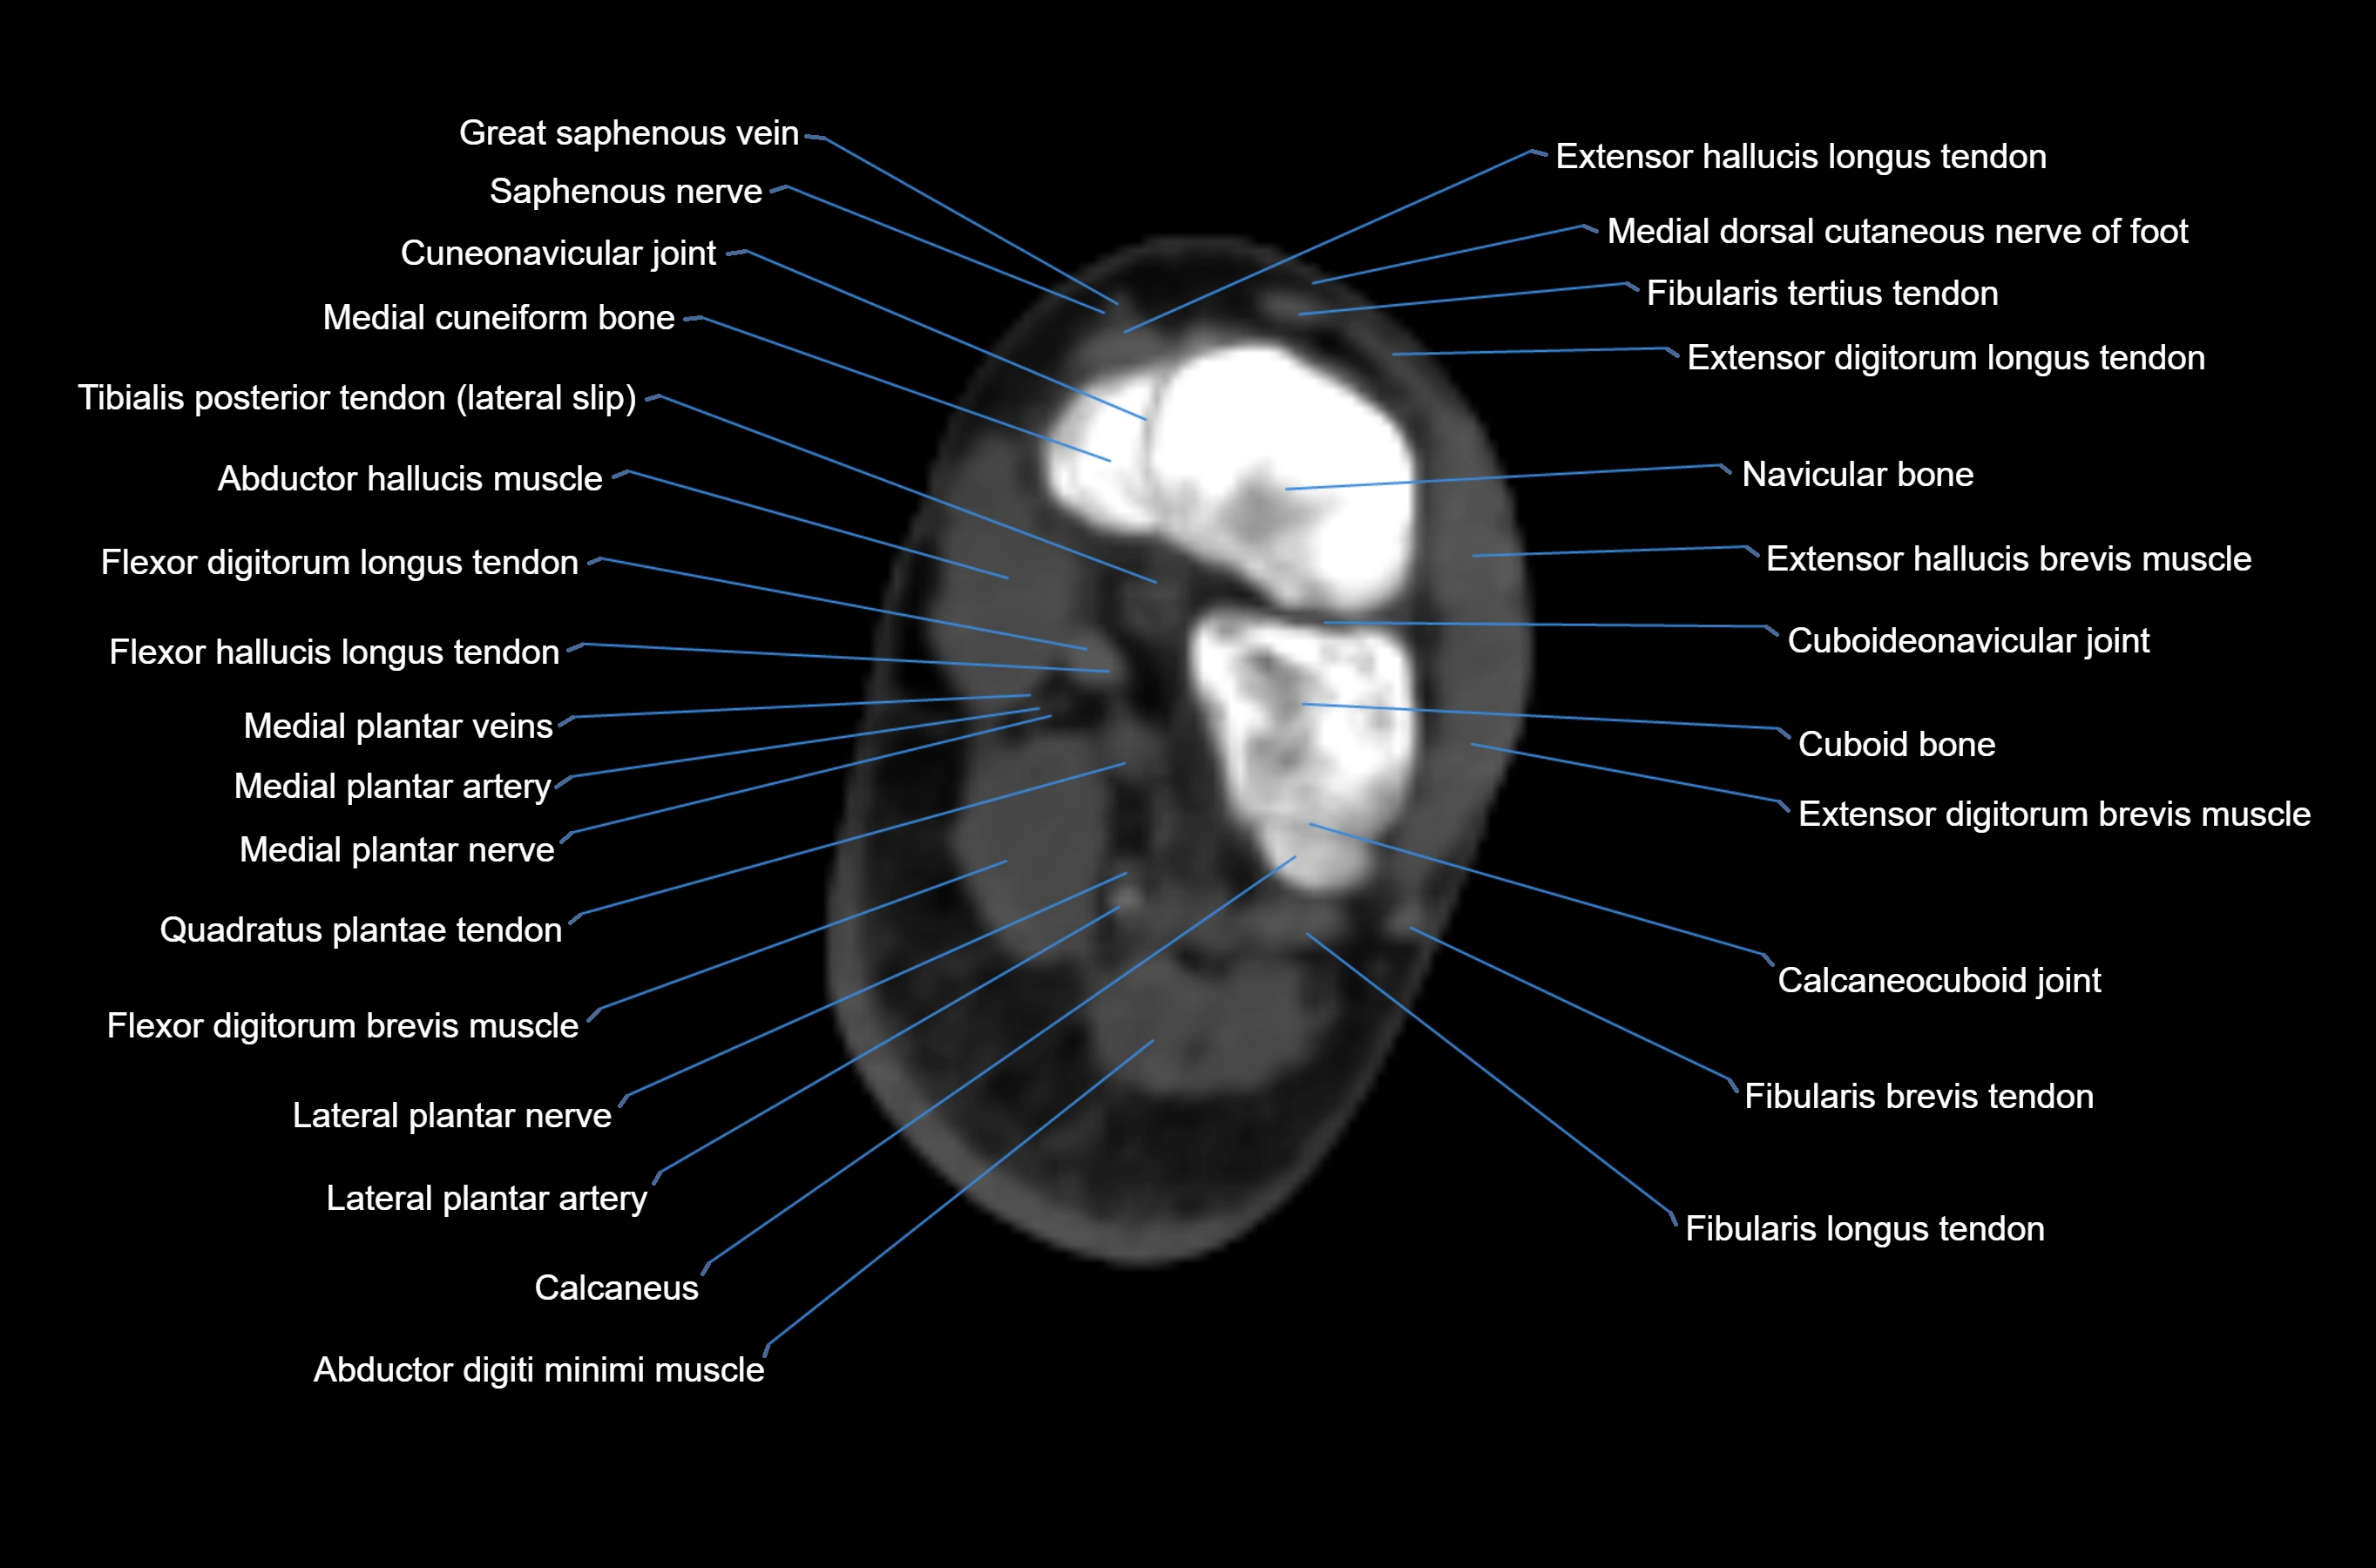

CT image